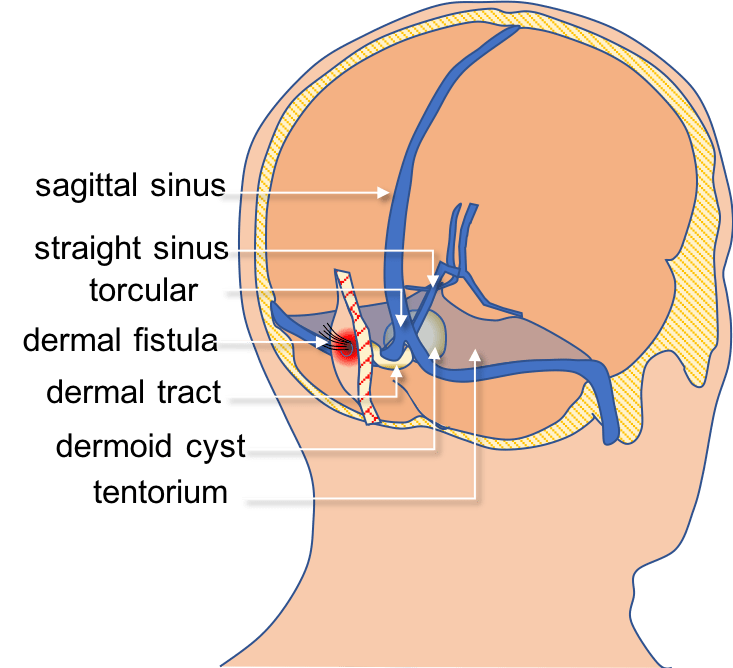

ces fistules peuvent se révéler par:

- une anomalie cutanée, vue à la naissance alors que les cheveux sont fins et transparents (A): c’est une fossette centrée par des cheveux plus épais et sombres

- plus tard par une infection locale, voire une méningite

- parfois, elles se présentent comme une masse intracrânienne (C, D) par accumulation de squames d’épiderme (kyste dermoïde)

l’imagerie montre un pertuis osseux (B), rarement une masse intracrânienne (C, D)

la chirurgie doit obtenir une exérèse complète du trajet fistuleux sous peine de récidive d’écoulement et d’infection chronique. lorsque le kyste se prolonge en intra-crânien, c’est un geste neurochirurgical majeur.

la chirurgie est en grand partie exploratoire car l’imagerie permet mal de juger de l’extension en profondeur de la fistule ; celle-ci peut se terminer au contact de la dure-mère, entre ses couches externe et interne, au plan arachnoïdien, voire être fusionnée avec le cervelet ou le tronc cérébral.

la dissection du trajet fistuleux d’avec le torcular est un temps délicat car il peut exister des adhérences intimes avec une paroi veineuse amincie, le trajet passant dans un dédoublement de la dure-mère ; cette adhérence peut se poursuivre le long de la face inférieure du sinus droit.

il est impératif de réaliser une éxérèse totale du trajet et du kyste dermoïde, surtout si la fistule est infectée, sous peine de récidive.